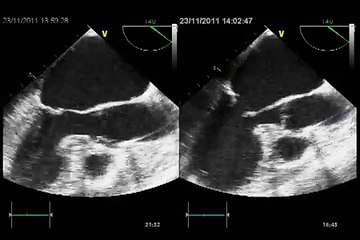

Mitral Regurgitation II (Revisited) - Color Doppler Echocardiogram - Dog

Duration: 00:15